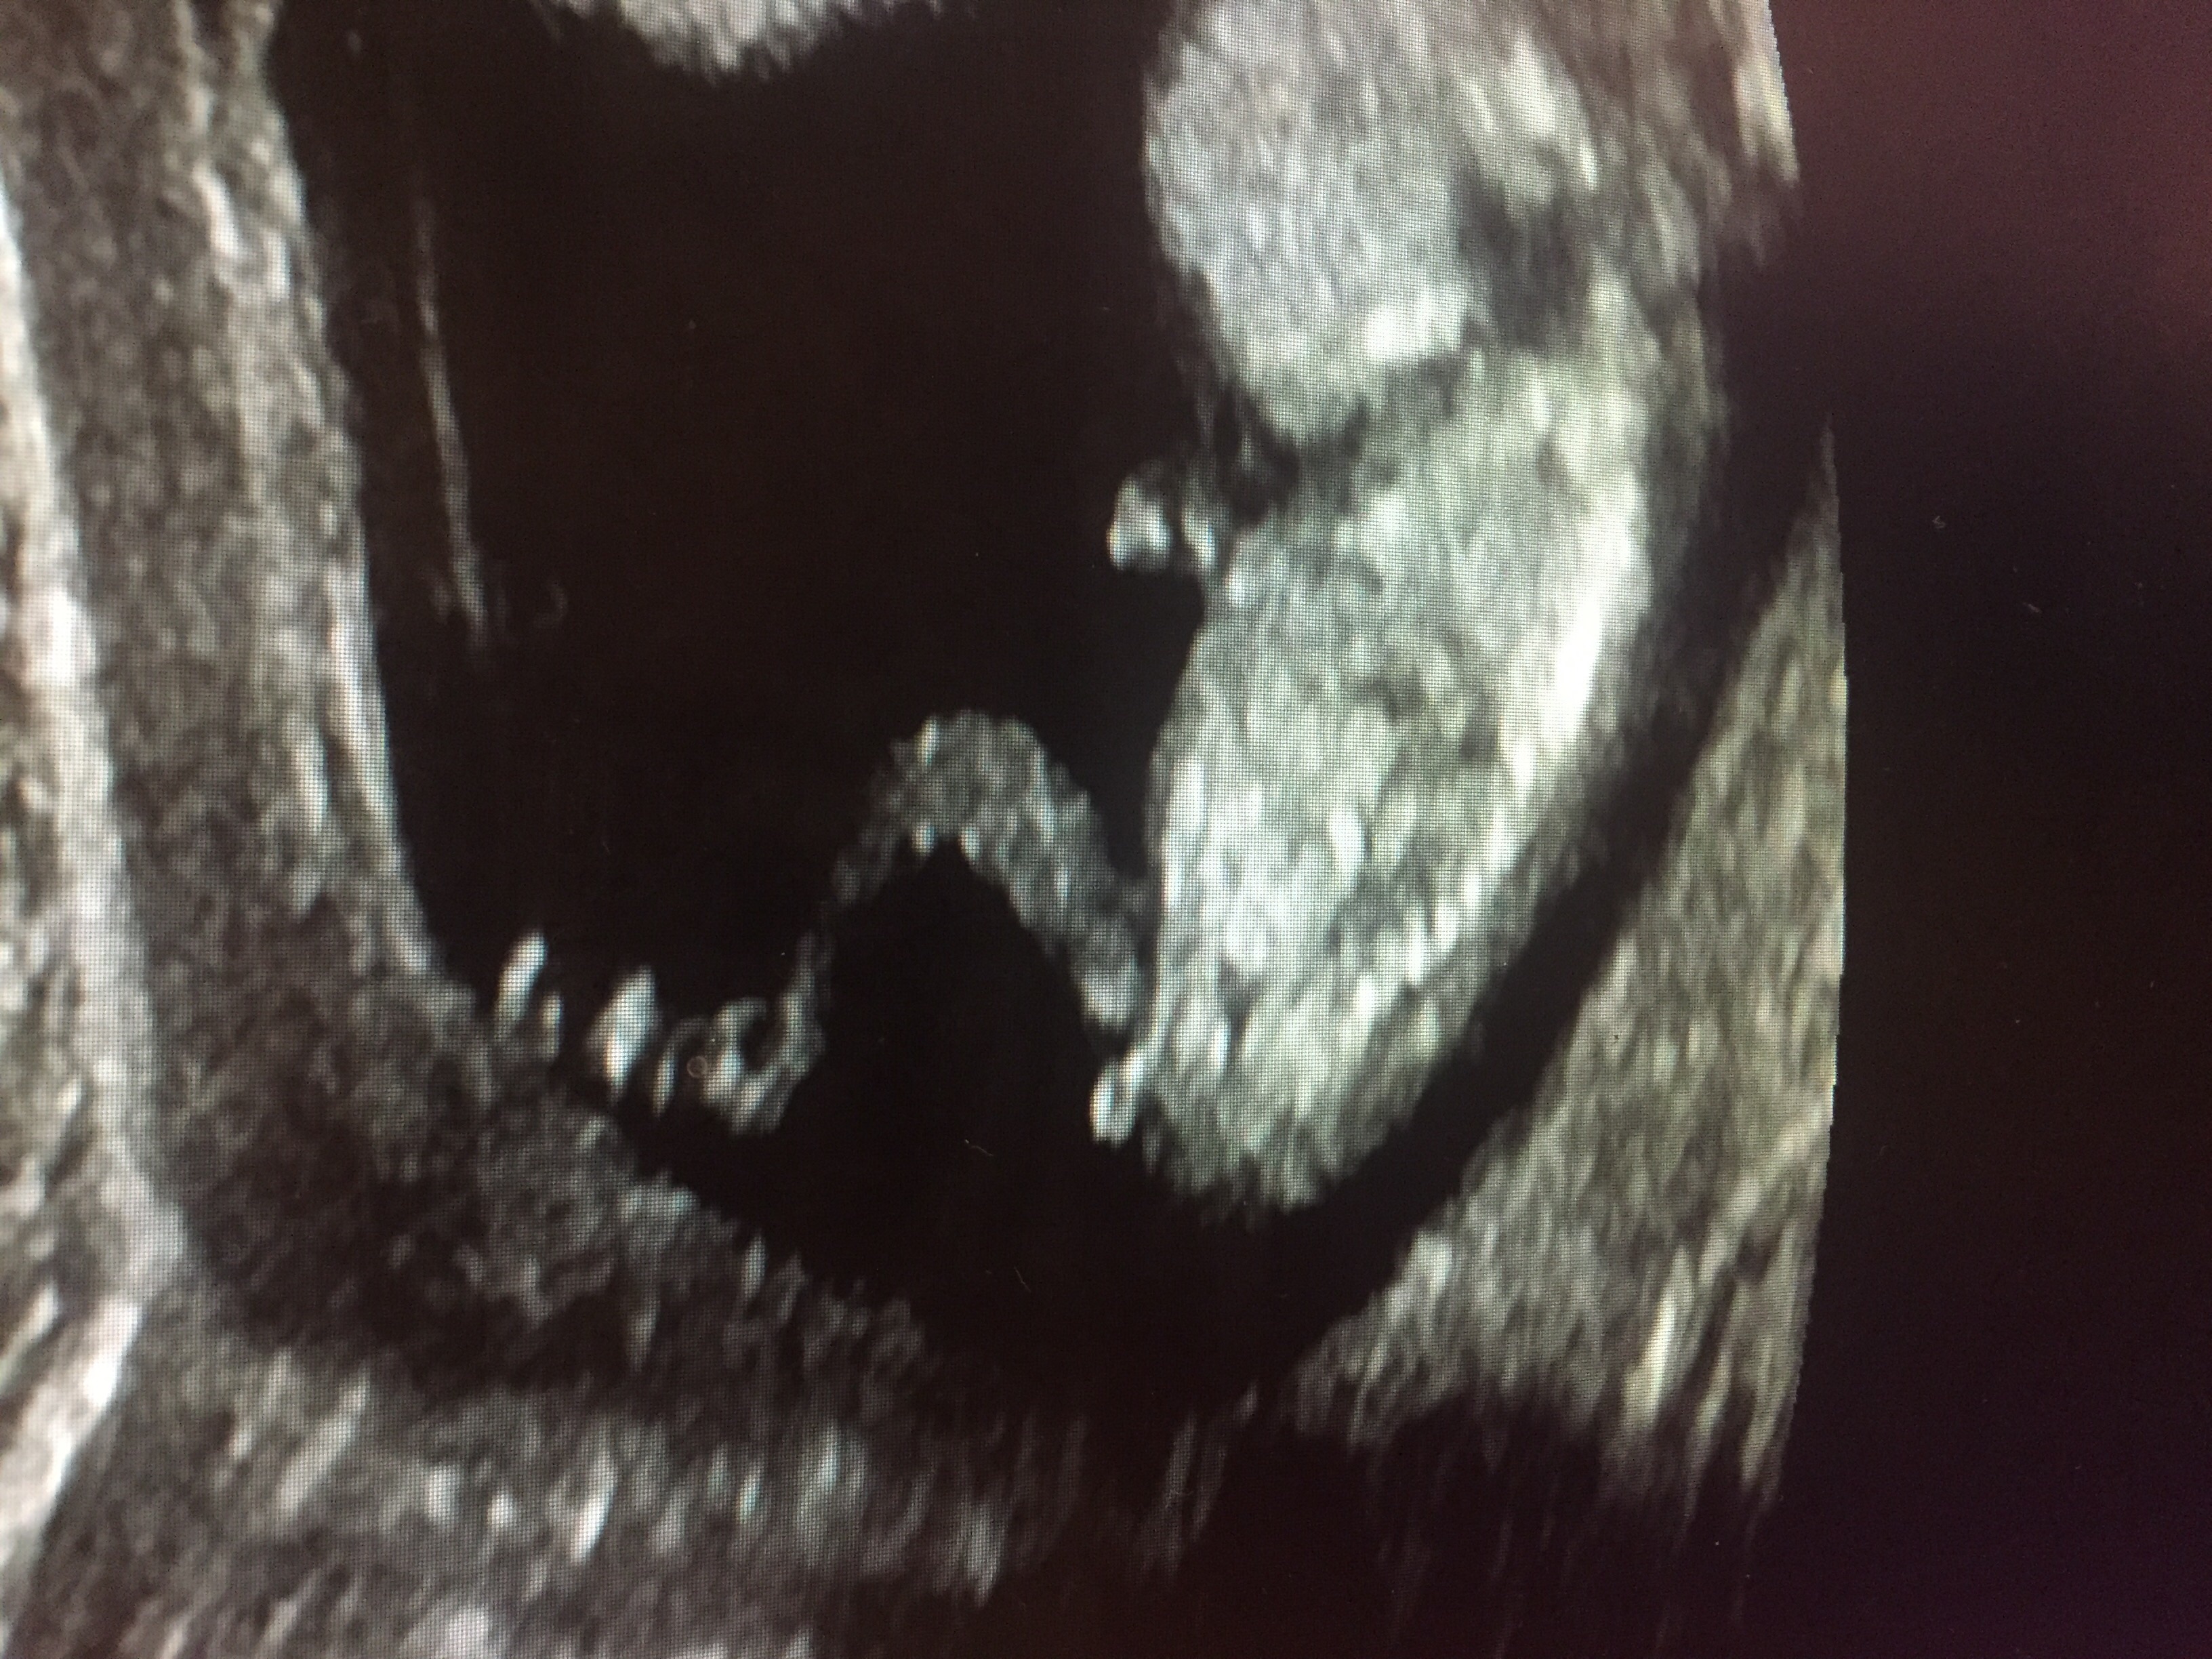

Thank you for the guesses! I will update when we find out for sure

Any more guesses?! We find out this weekend!!